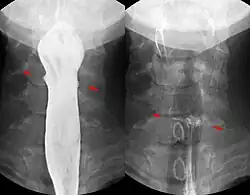

Knochensplitter oder Fischgräten können nach dem Verschlucken in die Schleimhaut des Schlunds oder der Speiseröhre eingespießt werden und dort zu Entzündungen führen. Verschluckte Fremdkörper, die in den Magen gelangt sind, gehen je nach Größe meist auf natürlichem Wege wieder ab. Bezoare (Trichobezoare, etwa eigene Haargeschwülste beim Menschen, und bei Tieren aus Pflanzenfasern gebildete Phytobezoare) können als Fremdkörper die Magen-Darm-Passage behindern.[1] Bei Knopfzellen wird die Entfernung aus dem Magen empfohlen, da eine Zerstörung der Hülle durch die Magensäure und ein Freiwerden giftigen Inhalts befürchtet werden muss. Grundsätzlich ist eine Entfernung bis in den oberen Dünndarm mittels Endoskopie möglich.

Zu versehentlich verschluckten Fremdkörpern, die nicht selten zu gastrointestinalen Perforationen führen, gehören Zahnstocher, Knochen, sowie Holzstäbchen von Rollmöpsen und Rouladen.[2]

Magnetische Fremdkörper: Wenn magnetische Kleinteile (z. B. aus einem Magnetbaukasten) verschluckt werden, besteht die Gefahr, dass sich diese aufgrund ihrer Anziehung zueinander oder zu einem anderen verschluckten Eisenteil festsetzen. Ein normaler Abtransport ist dann oft nicht möglich. Es kann auch zur Anziehung von zwei Magnetteilen in zwei verschiedenen Darmschlingen kommen, so dass es dazwischen zu einer Druckschädigung des Darmes in kurzer Zeit letztlich mit Darmperforation desselben kommt. Daher wird eine gesondertes Vorgehen bei Verschlucken von mehr als einem magnetischen Fremdkörper empfohlen, was in vielen Fällen auch die operative Entfernung der Magnete einschließt.[3][4]